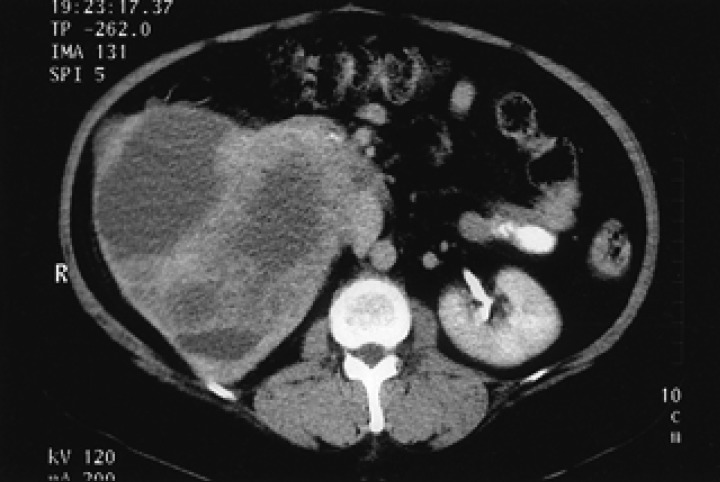

A 52-year-old woman had a 2-week history of right flank pain and intermittent hematuria with iron deficiency anemia. Physical examination of the patient was unremarkable, except for an abdominal mass and CVA tenderness. Laboratory data were as follows: white blood count 8,280/µL, platelet 346,000/µL, hemoglobin 9.5 g/dL, MCV 74.3 fl, MCH 24.4 pg, MCHC 32.8 g/dL; serum blood urea nitrogen 12.7 mg/dL, serum creatinine 0.89 mg/dL. Urinalysis showed microscopic hematuria. A computed tomography (CT) scan of the abdomen revealed a relatively well defined, large heterogeneous tumor in the right kidney (Figure 1). CT scans of the brain and chest, as well as a bone scan were carefully examined to look for signs of metastatic disease. There were no evident metastases at regional lymph nodes or at any distant organs. The preoperative impression was a renal cell carcinoma; the patient underwent a right radical nephrectomy. Macroscopically, a very large mass measuring 10×15 cm, from the right kidney, was identified (Figure 2). Cut sections were grey-yellow in color and contained bloody and serosanguinous fluid. The tumor penetrated the capsule, but there was no infiltration into the renal pelvis, hilus of the kidney or adjacent lymph nodes. Histological examination revealed a pure small cell carcinoma with scant cytoplasm and stippled nuclear chromatin (Figure 3A). Immunohistochemical stains revealed that the tumor cells were strongly positive for synaptophysin, weakly positive for chromogranin, and negative for S-100, leukocyte common antigen (Figure 3B, 3C). We concluded that this case represented a pure small cell carcinoma of the kidney. Postoperatively, the patient received six courses of adjuvant chemotherapy consisting of etoposide and cisplatin. Upon completion of the chemotherapy, all oncological investigations, including abdominopelvic CT and chest X-ray, revealed no evidence of recurrence. Outpatient follow-up of laboratory and radiographic studies were performed at regular intervals. The patient is currently well without any evidence of recurrence at 28 months following the primary diagnosis.

Figure 1

Contrast enhanced CT of the abdomen reveals a large, complex heterogeneous mass in the right kidney without retroperitoneal lymphadenopathy.